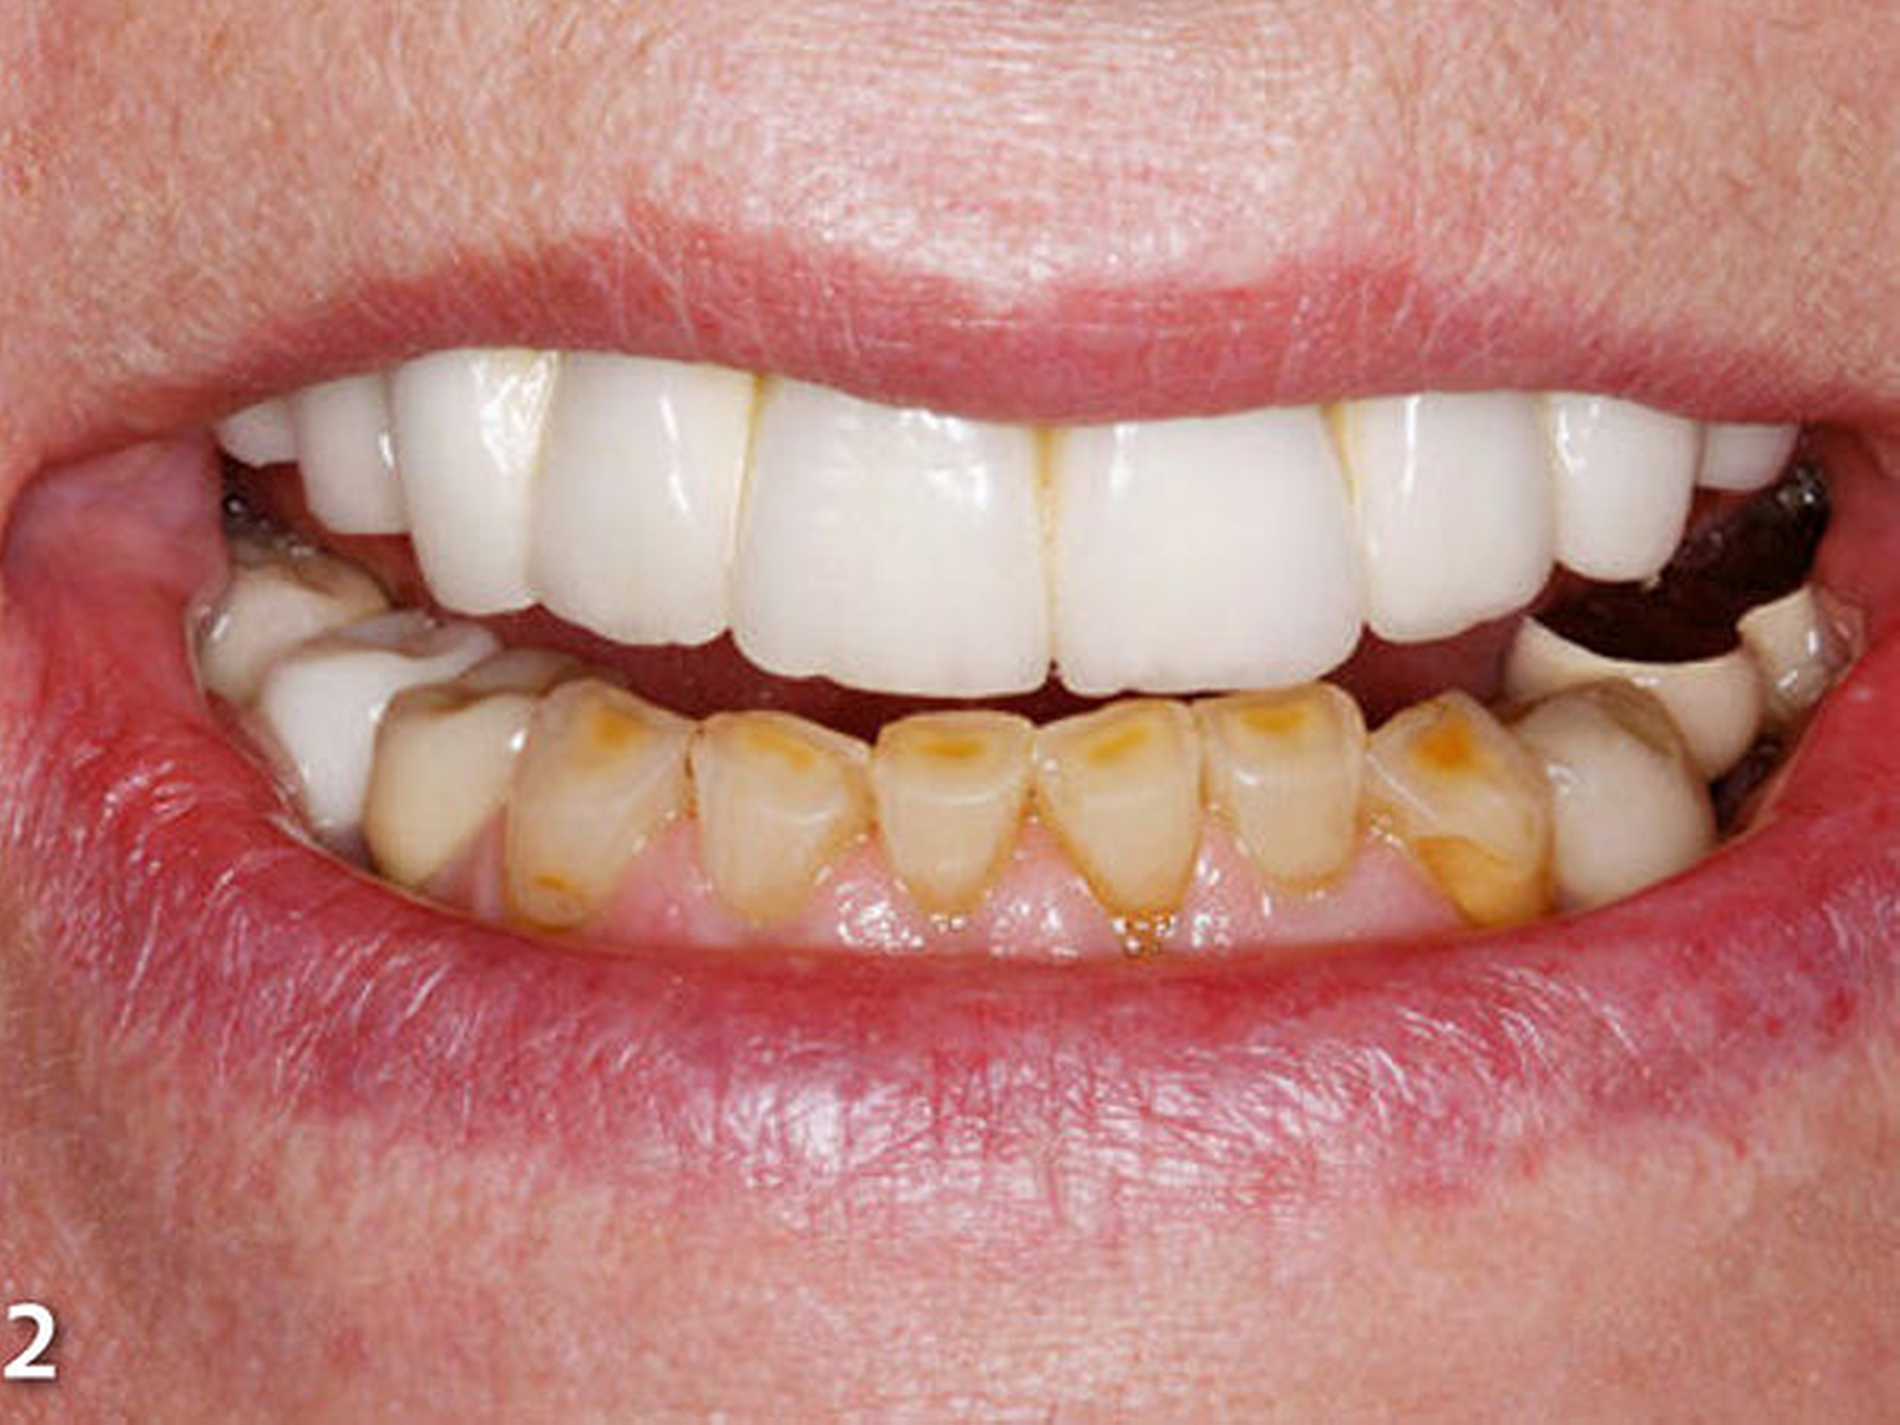

Die Patientin wies deutliche Zeichen von Attrition und Abrasion an den Unterkieferfrontzähnen (Abb.2) und ein Defizit in der vertikalen Distanz der Okklusion auf (Abb.3). Im Unterkieferfrontzahnsegment war eine kompensatorische Eruption des Kieferkamms in Richtung Okklusionsebene eingetreten, die verbreiterte keratinisierte Gingiva gibt darauf einen deutlichen Hinweis (Abb.4) (Bartlett & Smith 2000; Berry & Poole 1976; Cekic Nagas &Ergun2015; Manfredini & Poggio 2016).

Dies ist für die Planung von Rekonstruktionen ungünstig, da somit in den meisten Fällen zu wenig okklusaler Platz vorhanden ist (MericskeStern 2007). Sämtliche Unterkieferfrontzähne standen in der statischen Okklusion in festem Shimstockfolienkontakt zu den Antagonisten im Oberkiefer. Aufgrund der großflächig freiliegenden Dentinareale im Bereich der Inzisalkanten berichtete die Patientin auch über Hypersensibilitäten auf thermische und chemische Reize.

Insbesondere störten die Patientin aber der gravierende Farbunterschied der Unterkieferfront zu den Keramikverblendungen der Rekonstruktionen des Oberkiefers und die Form bzw. Größe der unteren Frontzähne (Abb.5). Darüber hinaus entsprachen die insuffizient ausgeformten Kauflächen der Restaurationen der Unterkieferseitenzähne nicht den Anforderungen an eine funktionsorientierte Gestaltung der okklusalen Anatomie (Abb.6).